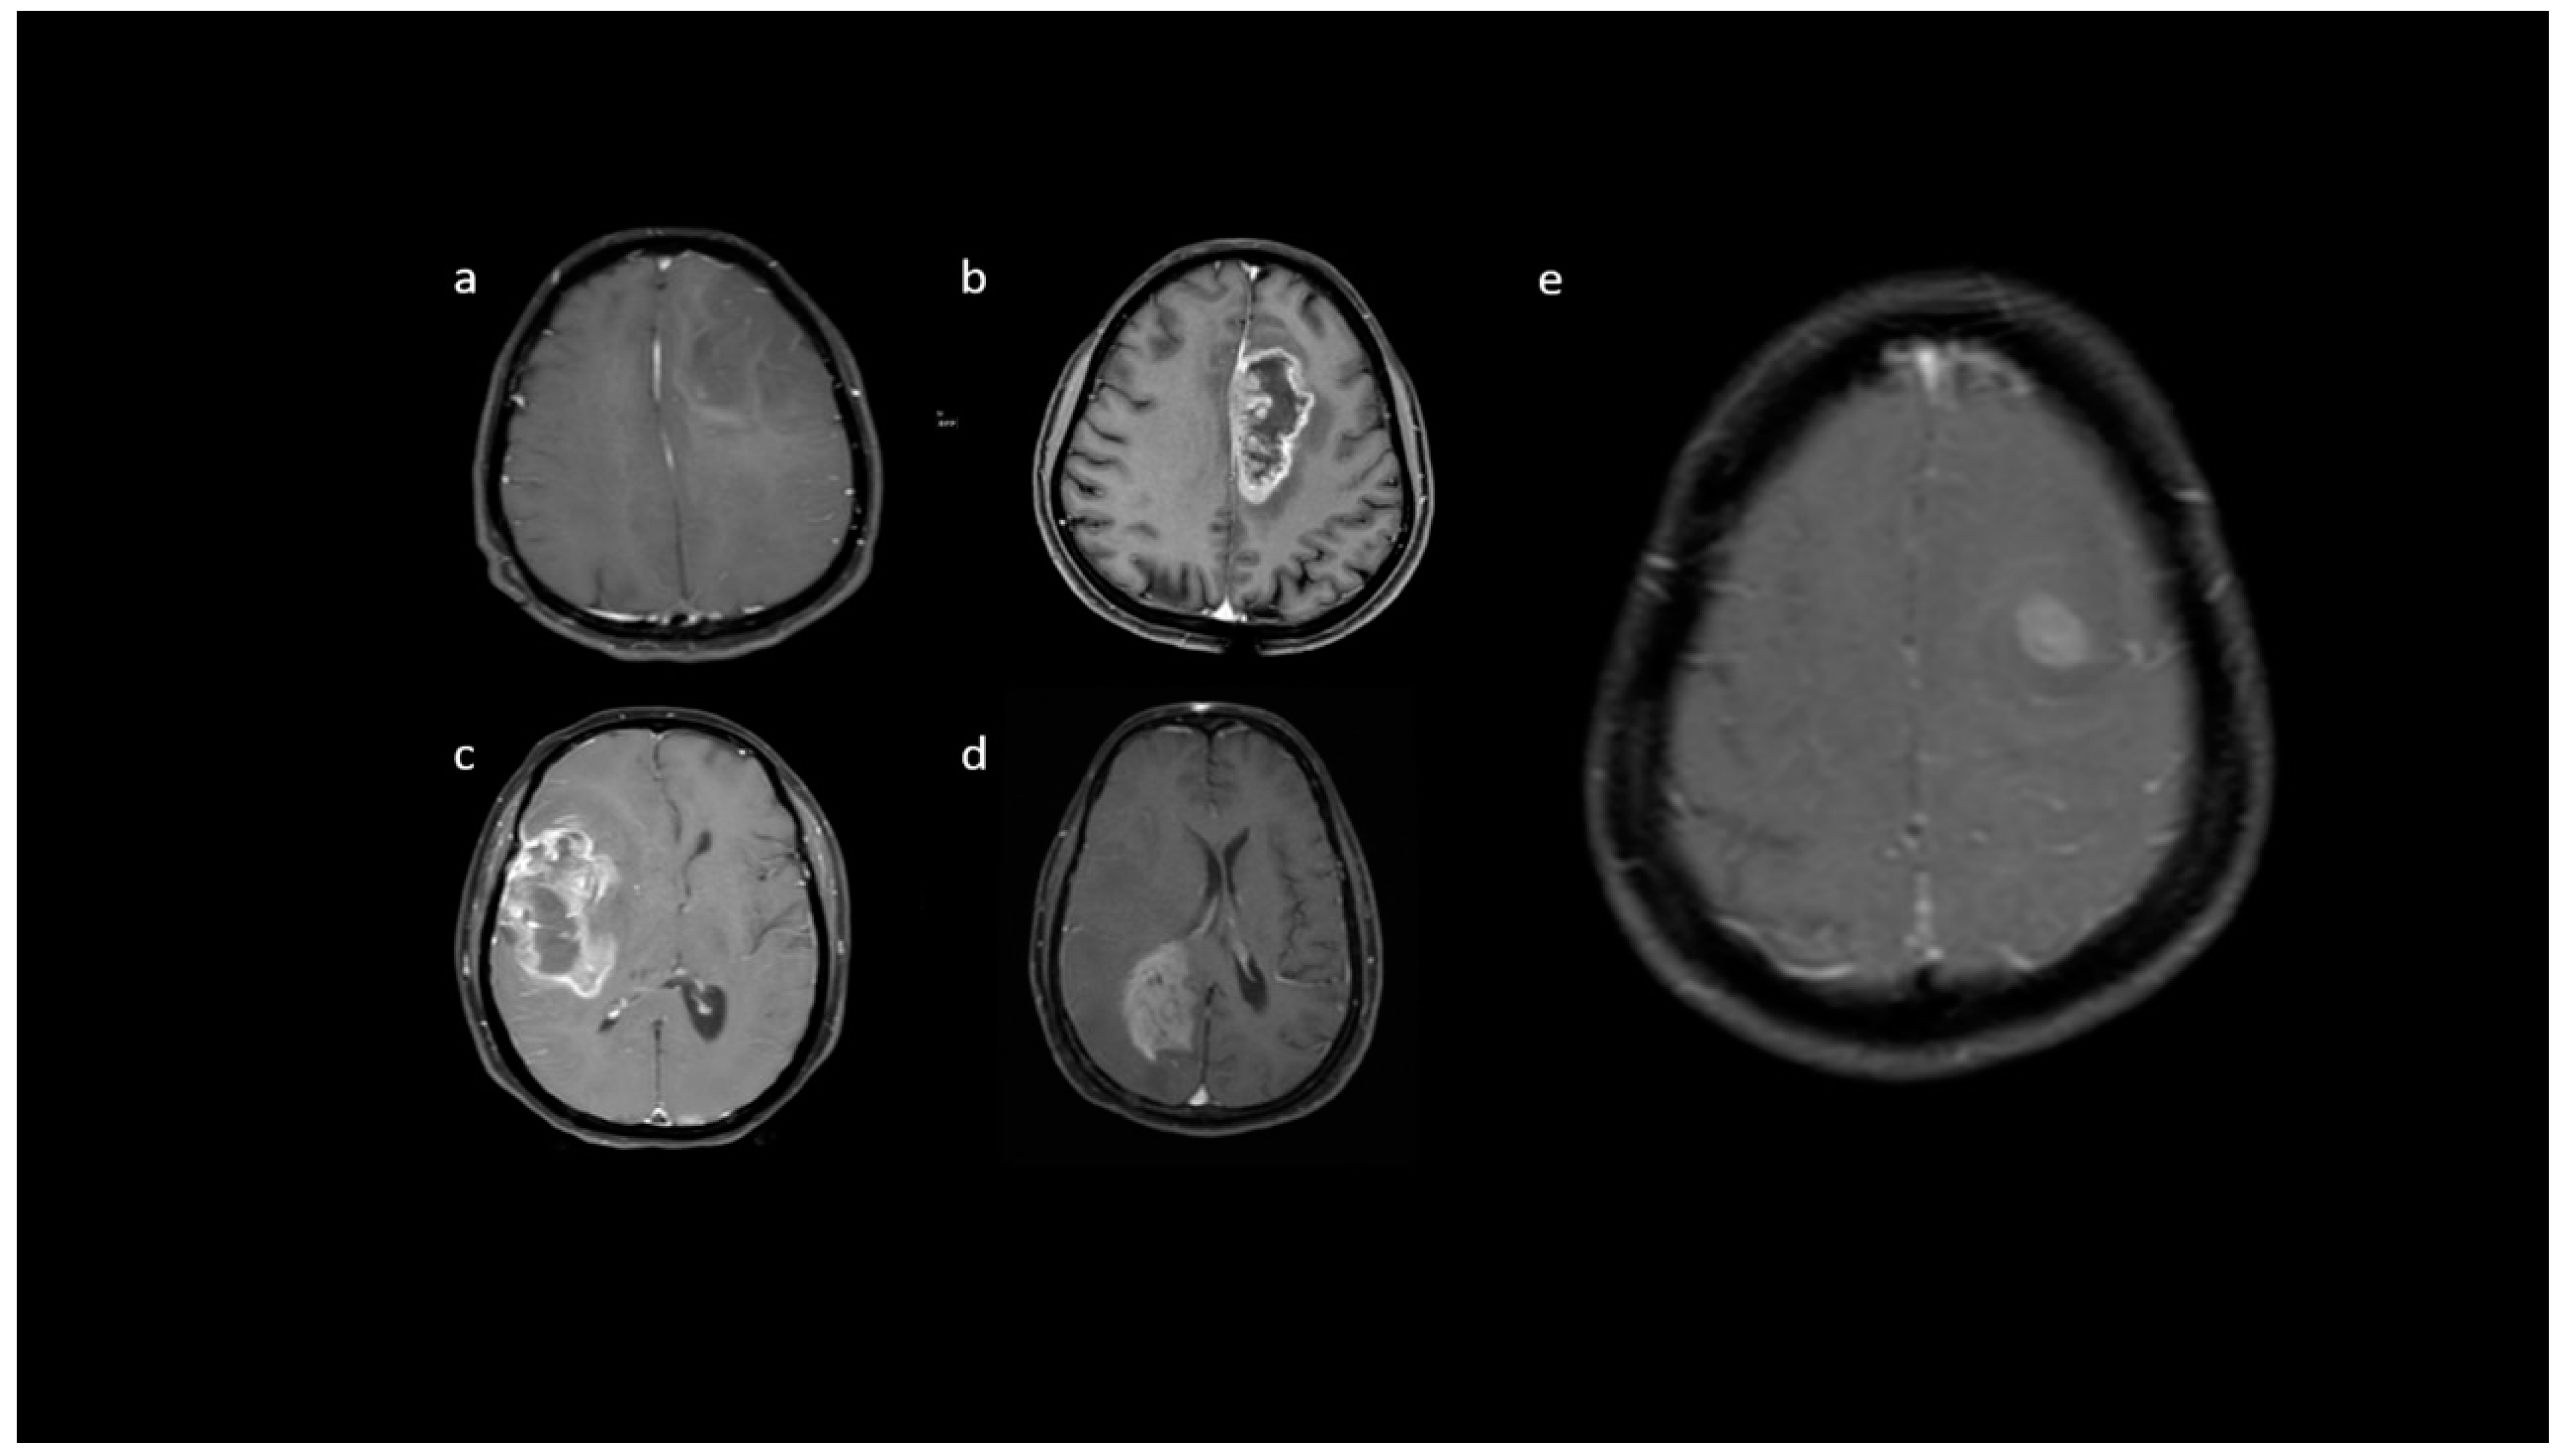

3.2. MRI Parameters of IDH-Wildtype vs. Mutant Phenotype Tumors

| Enhancement I | Mild | 9 (47.4) | 5 (3.9) | <0.001 |

| Moderate | 6 (31.6) | 25 (19.4) | ||

| Severe | 4 (21.1) | 99 (76.7) | ||

| Enhancement III | Rim | 6 (31.6) | 104 (80.6) | <0.001 |

| Nodular | 0 | 2 (1.6) | ||

| Patchy | 11 (57.9) | 13 (10.1) | ||

| Solid | 2 (10.5) | 10 (7.8) | ||